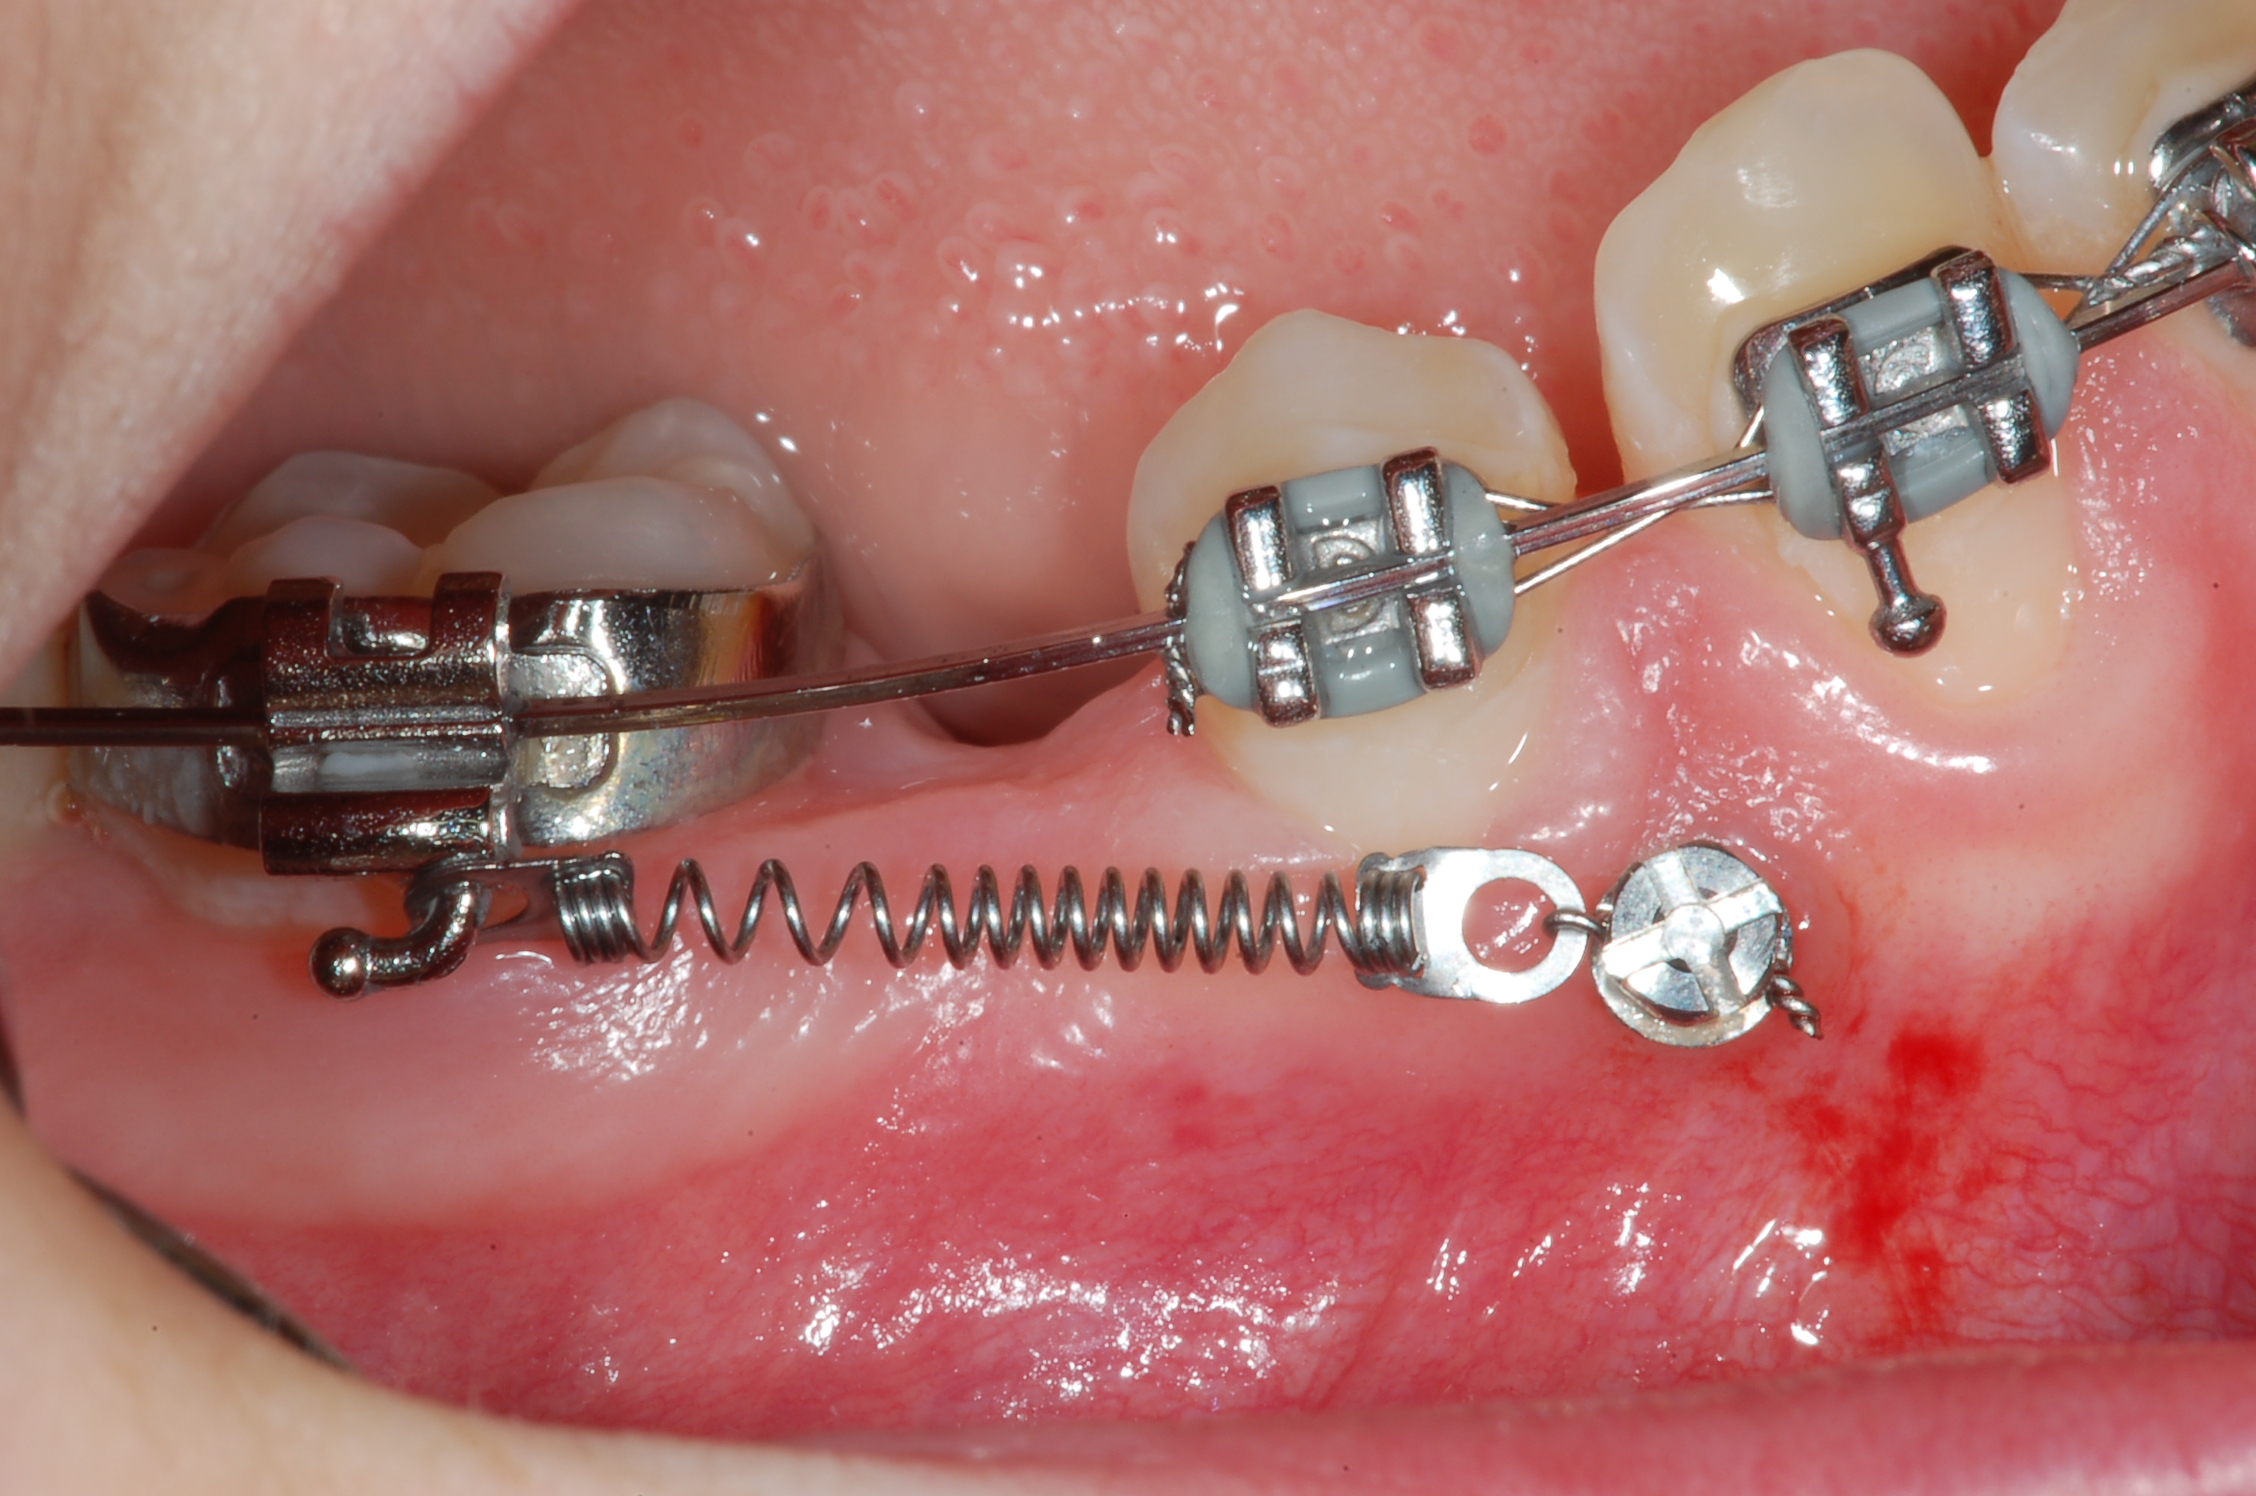

Mikroschrauben

Mikroschrauben stellen eine innovative und bewährte Methode in der Kieferorthopädie zum Erreichen einer maximalen Verankerungssituation bei der Behandlung mit einer festen Spange dar.

Die Schrauben bestehen aus Titan und sind somit sehr körperverträglich.

Mikroschrauben werden dann angewendet, wenn man bestimmte Bewegungen von Zähnen mit der festen Spange ausführen muss und man einen zusätzlichen Halt benötigt, damit es nicht zu Wechselwirkungen auf die anderen bewegten Zahngruppen kommt. Als Beispiel sei hier ein einseitiger Lückenschluss bei fehlenden oder nicht angelegten Zähnen genannt.

Das Einbringen der Schrauben erfolgt schmerzarm unter Lokalanästhesie, ohne dass ein Schnitt gesetzt werden muss.

Nachdem die Schraube in den Kiefer eingebracht ist, kann man sie nach einer kurzen Einheilungszeit belasten. Das Entfernen der Schraube nach der Behandlung kann ohne Betäubung erfolgen.